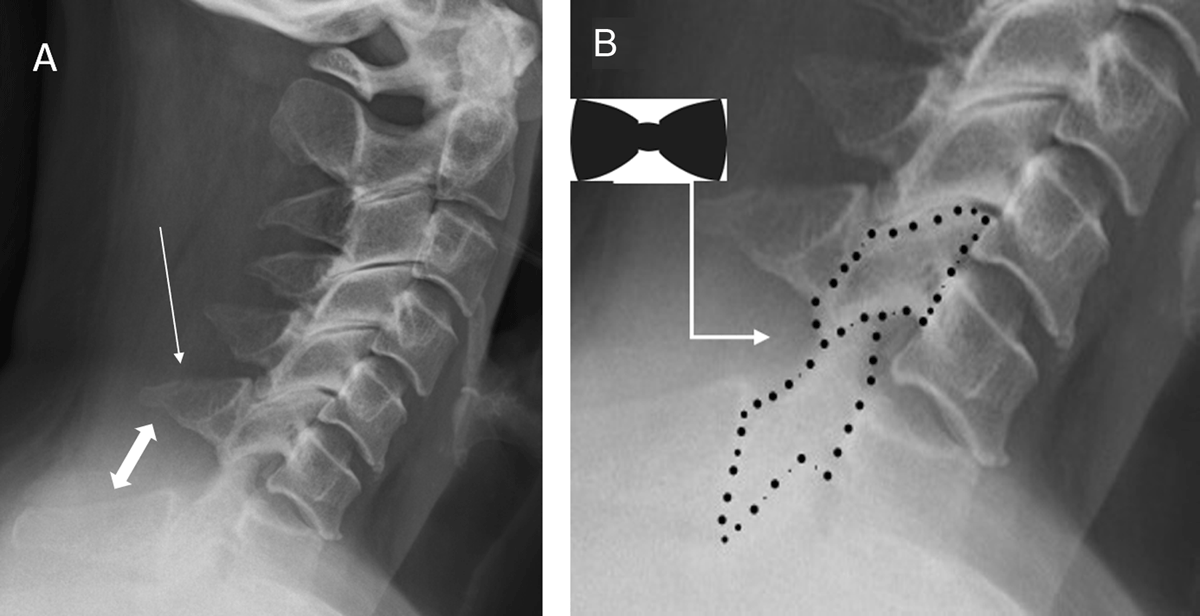

Figure 1

Bow-tie sign and laminar space sign.

Lateral radiograph of the cervical spine (A) of a 33-year-old man following a fall from an electric scooter shows a grade I anterolisthesis with less than 25% anterior translation of C6 on C7 vertebrae. In addition, there is an oblique fracture across the spinous process of C6 vertebra, which is consistent with clay-shoveler fracture (single-headed arrow). Besides focal kyphosis and reduced overlap of the articular processes, there is fanning or widening of the interspinous distance (double-headed arrow).

The laminar space (which is the distance between the spinolaminar line and the posterior surface of the articular pillars) widens progressively from C3 to C6 level. It changes abruptly and narrows at the C7 level (B). These changes indicate a sudden rotational injury at C6–7 level. Displacement of the interfacetal joint with rotational deformity at this level produces a “bow-tie” appearance and a “double-appearance” of articular facets above the C6–7 level.